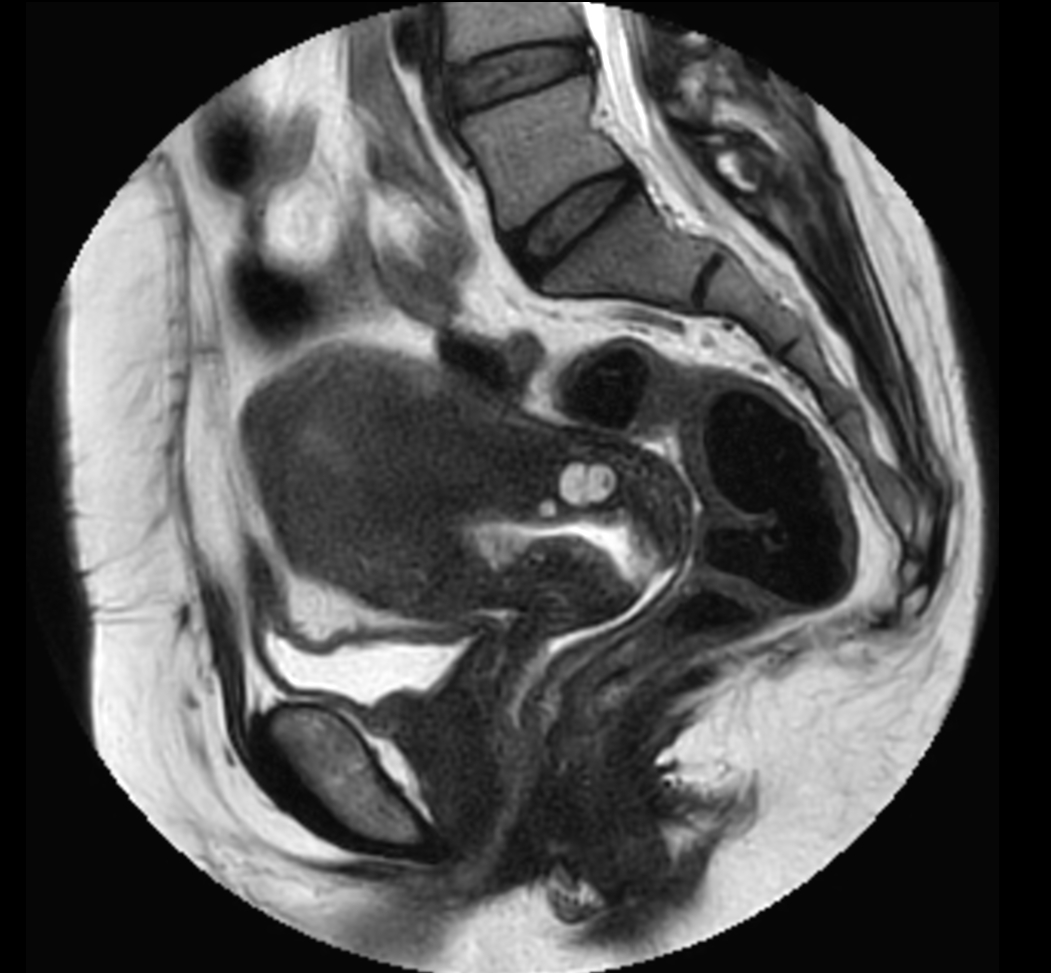

Sagittal MultiVane XD - T2w TSE

Coronal MultiVane XD - T2w TSE